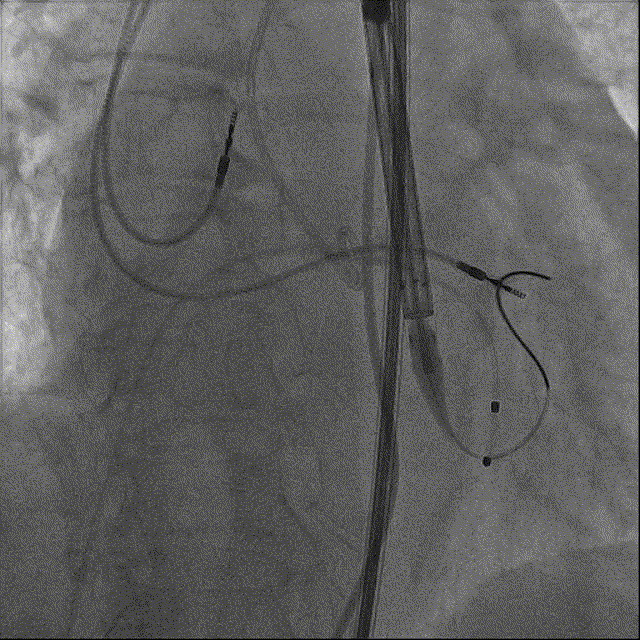

瓣膜回收后,再次定位释放

22mm球囊后扩